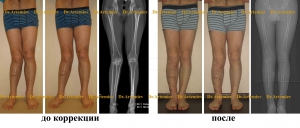

Férfi 24 éves. Varus deformitás a térd.

A férfi 21 éves. Varus deformitás a lábszár.

Férfi 26 éves. Varus deformitás + subluxation fejét a fibula.